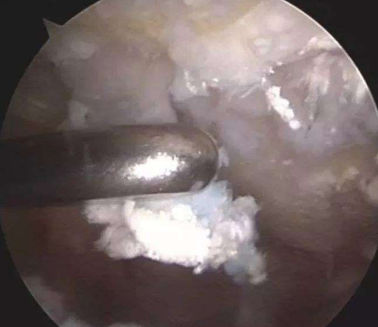

关节镜取石:关节镜是微创手术,在创口小的时候,有良好的手术视野,能够通过冲洗和切割,清除关节周围的结晶石,患者恢复时间也很短。

关节镜取石